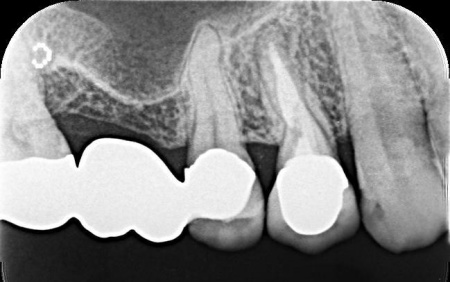

60代男性 歯に合わなくなった被せ物をジルコニアクラウンに交換した症例

拝見したところ、右上4番目の歯には白い被せ物が入っていましたが、加齢により歯ぐきが下がったことで被せ物が合わなくなり、土台が見えて黒くなっていました。

この歯は笑ったときに見えやすい部分のため審美性に影響が出ており、さらにこのまま放置すると隙間から細菌が入り込んで虫歯が再発するリスクもあります。

この歯は過去の治療で被せ物を装着する際に歯の神経を取る根管治療を行っていました。

根管治療後の歯は時間が経過すると根の周りに炎症を起こすことがあります。

炎症が起きた際には根管治療からやり直す必要があるものの、今回は特に問題は認められなかったため被せ物の交換のみで対応できることも併せて説明しました。